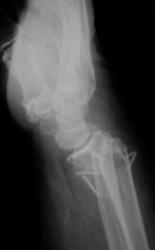

Катенёв Валенти... Дата публикации 23.04.2009, 18:55 Травма. Пациентка направлена на рентгенографию правого лучезапястного сустава. Проведена рентгенография, насколько это возможно, в стандартных проекциях. После репозиции отломков и наложения гипсовой повязки произведено рентген-контроль. Чт, 23/04/2009 - 19:21 #1 Dr.Mario Не на сайте Был на сайте: 11 лет 6 месяцев назад Зарегистрирован: 06.08.2008 - 08:44 Публикации: 920 плохо, очень плохо. Let me see... radiographia.ru Чт, 23/04/2009 - 20:48 #2 Vega Не на сайте Был на сайте: 4 месяцев 3 недели назад Зарегистрирован: 22.01.2009 - 19:16 Публикации: 1087 Да, нужно оперировать

плохо, очень плохо.

Да, нужно оперировать